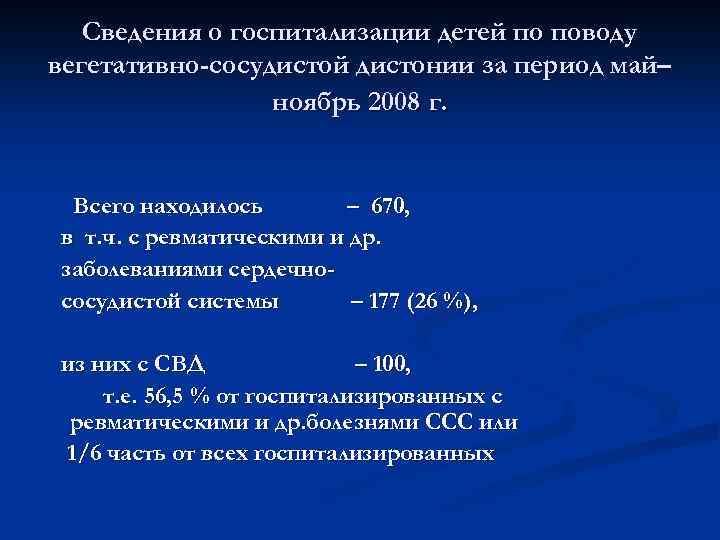

Сведения о госпитализации детей по поводу вегетативно-сосудистой дистонии за период май– ноябрь 2008 г. Всего находилось – 670, в т. ч. с ревматическими и др. заболеваниями сердечнососудистой системы – 177 (26 %), из них с СВД – 100, т. е. 56, 5 % от госпитализированных с ревматическими и др. болезнями ССС или 1/6 часть от всех госпитализированных